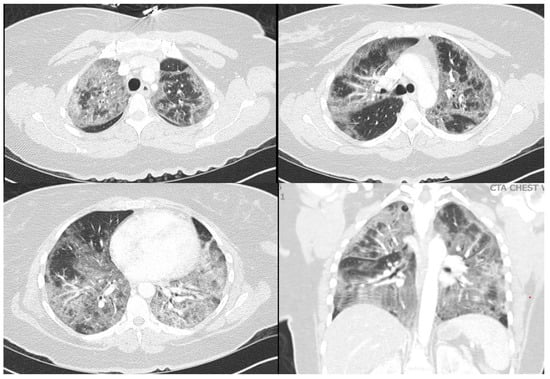

2. Case Report